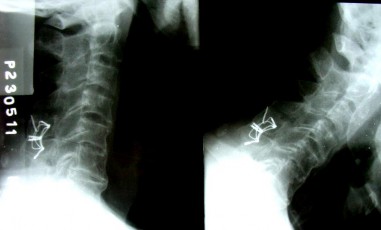

NGỬA CÚI

XOAY CƠ SAU CỔ

Tầm vận động cổ (ngửa, cúi, xoay) bình thường.

Cơ sau cổ không bị teo.